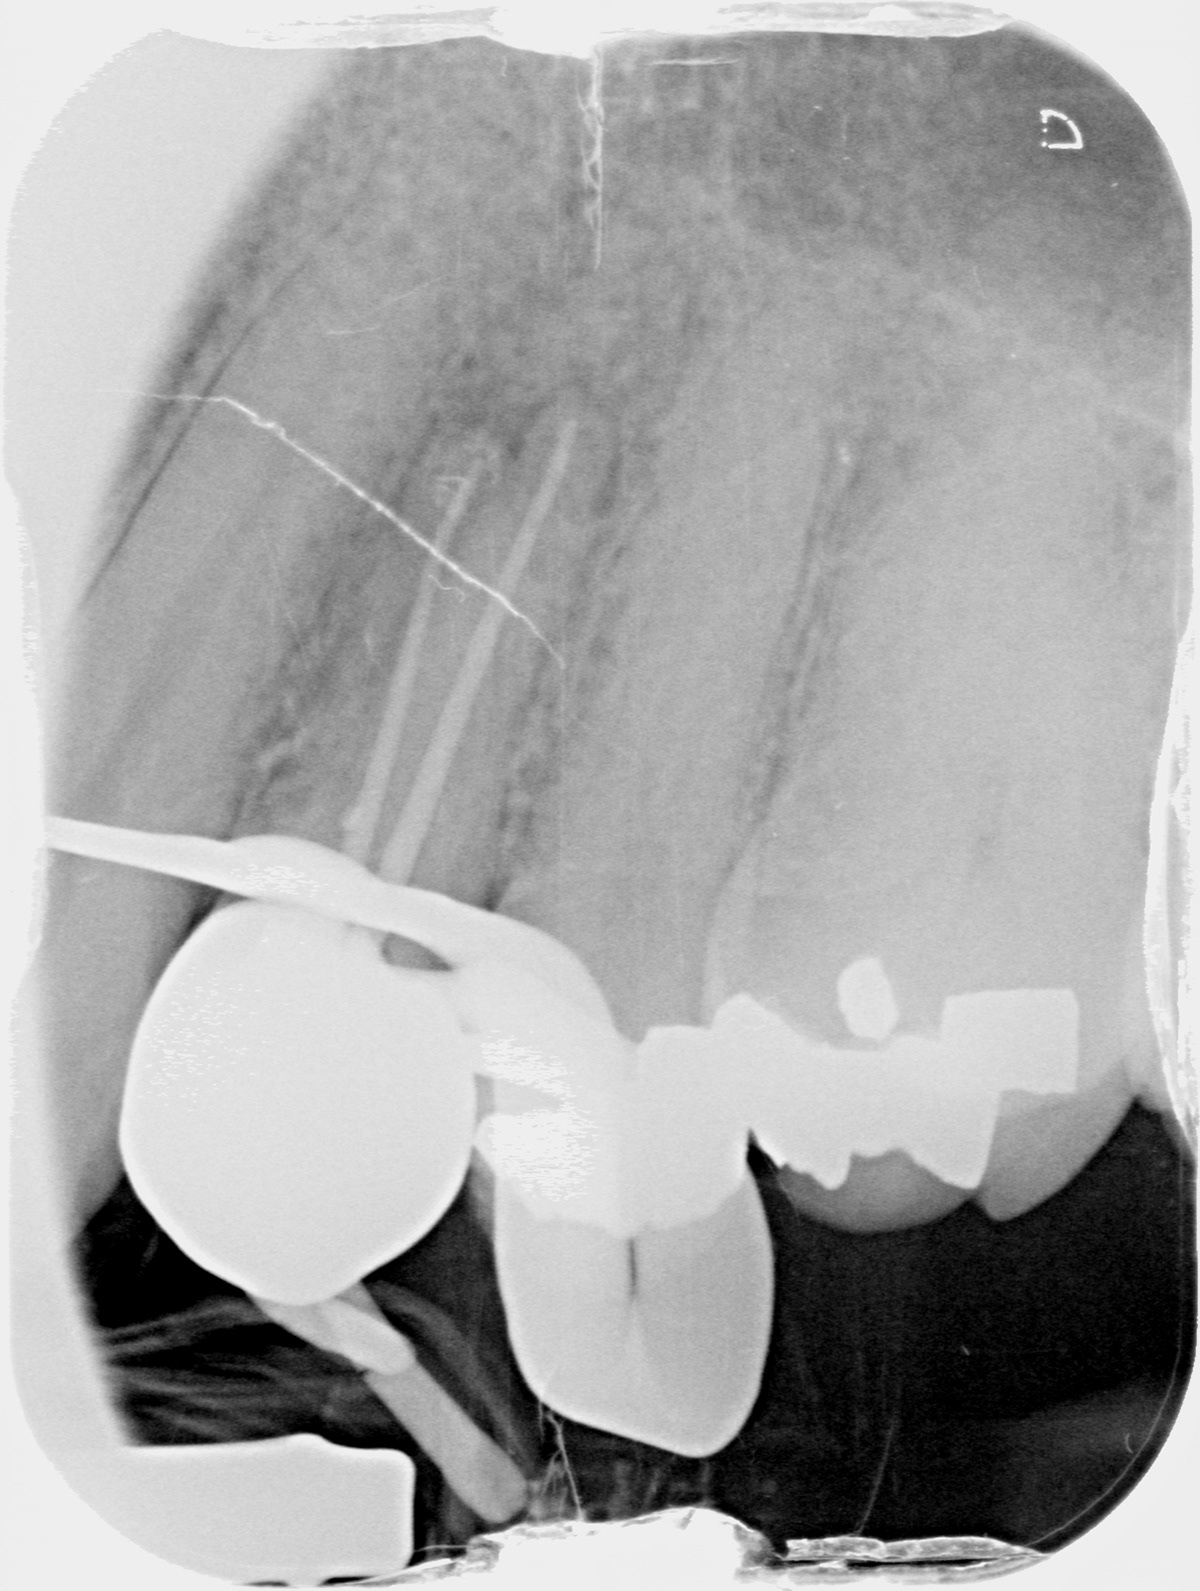

CURVES...

BEFORE

AFTER